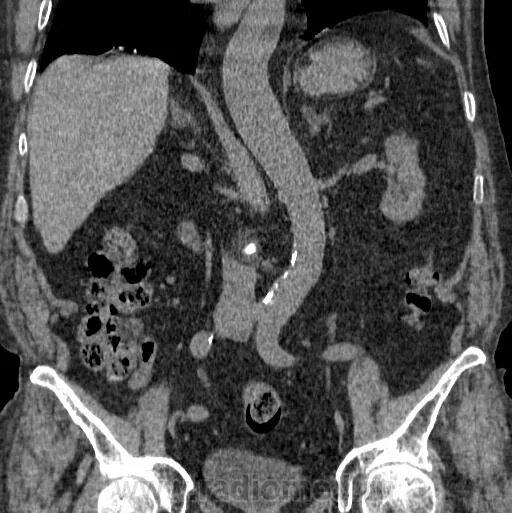

Гиперваскулярное образование почки что это такое